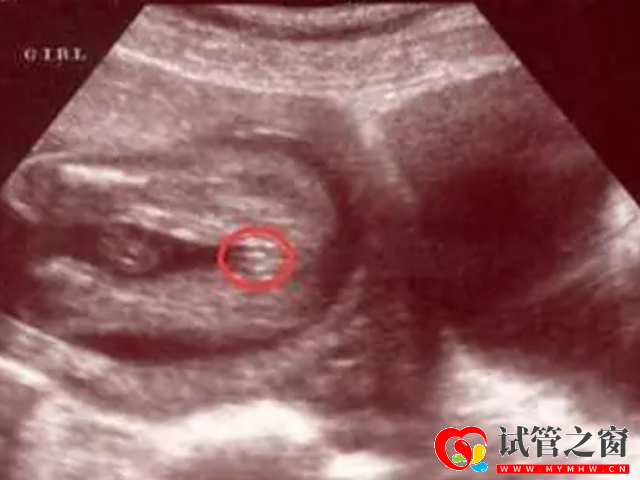

- 1. 可以看胎兒雙腿之間,如果說這個部位是有三條白線,而且呈小凹槽狀、圓圓的,大概率懷的是女孩,如果是凸出的東西,大概率是男孩;

通過四維彩超看男孩女孩的準確率是無法保證的,但是從科學的角度去看,準確率是在50%,因為生男生女的幾率各占一半。而對于這些通過四維彩超判斷性別的方法都是過來寶媽經驗總結,大家可以參考,但是切記不要過于當真。而且在檢查過程中,為了避免透露胎兒的性別,醫生會主動的回避胎兒的性別特征以及下半身,同時,在后期制作光盤時,也會將可能泄露胎兒性別的部分進行處理。所以單憑檢查數據、圖像判斷生男生女是沒有科學依據的。